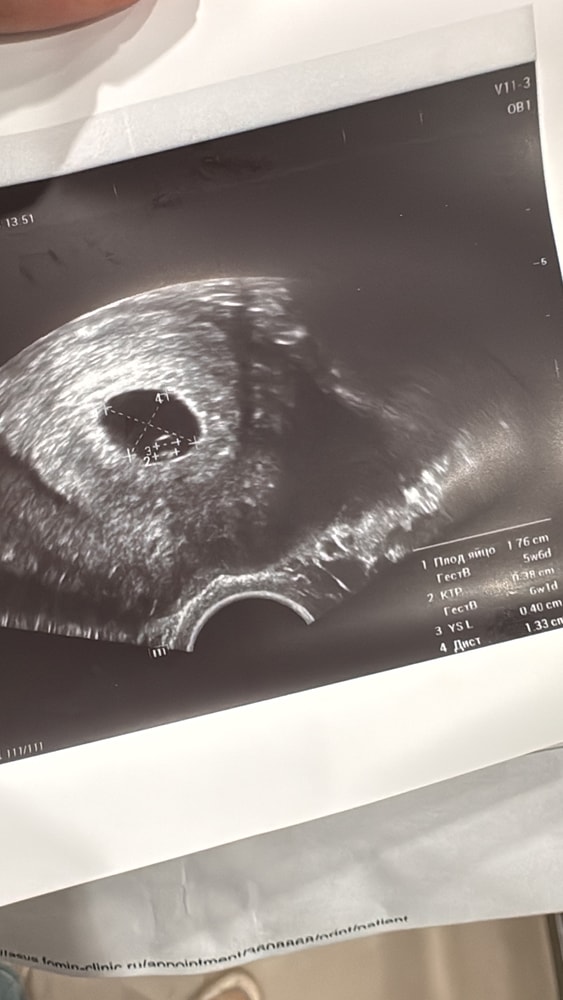

УЗИУх, это случилось. Срок 5,5 по месячным. По узи 6,1. Плодное яйцо 16 мм, эмбриончик есть и пульсирует 3,8мм😭😭😭😭

Конечно, есть повод побеспокоиться - маленькое желтое тело 11 на 14. Но врач вообще ничего про него не сказала. Имеет ли это какое-то значение?